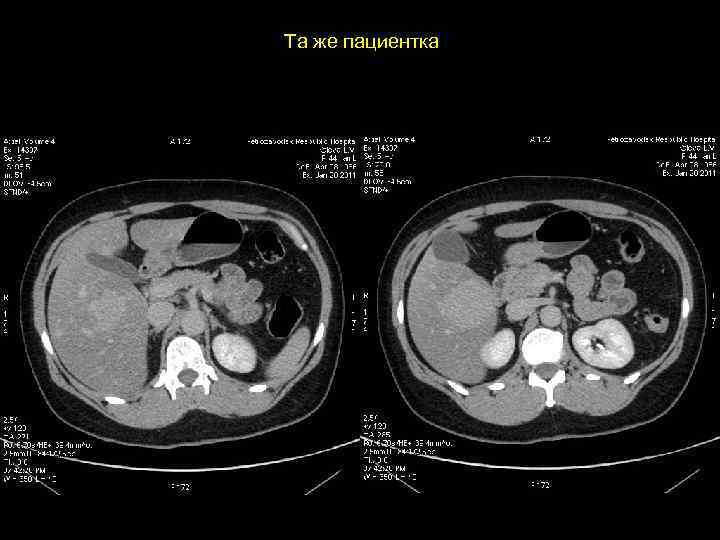

Клиническое наблюдение. Пациентка К, 1966 г. р.

Та же пациентка